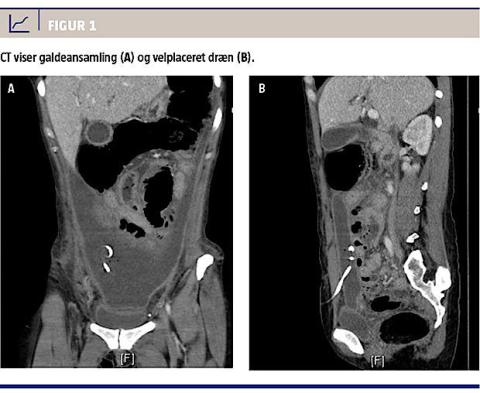

cystektomi. Patienten bedredes initialt, men fik på 18.-dagen igen smerter, stigende infektionstal og påvirket almentilstand. En CT viste nu cholascos, der strakte sig fra galdeblærestedet til nedre abdomen (Figur 1 A og B). En magnetisk resonanskolangio-pankreatografi viste sten i ductus choledochus. Der blev drænbehandlet med god effekt, og patienten blev udskrevet i velbefindende med plan om elektiv kolecystectomi og fjernelse af koledokusstenene. I ventetiden til dette blev patienten indlagt akut med intern herniering. Ved operation fandt man massive adhærenser og en lille skrumpet galdeblære, som var beliggende svært utilgængeligt i galdeblærelejet, hvorfor man ændrede strategi og senere udførte transgastrisk endoskopisk retrograd kolangiopan-